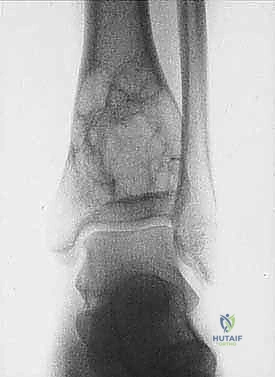

* الساركوما العظمية (Osteosarcoma): الأكثر شيوعاً، تظهر عادة حول الركبة (أسفل الفخذ أو أعلى القصبة).

| حدود الورم في الأشعة | واضحة، محددة بدقة (Sclerotic margin) | غير واضحة، متآكلة (Moth-eaten appearance) |

| اختراق قشرة العظم | نادر جداً | شائع جداً، يمتد للأنسجة الرخوة المحيطة |